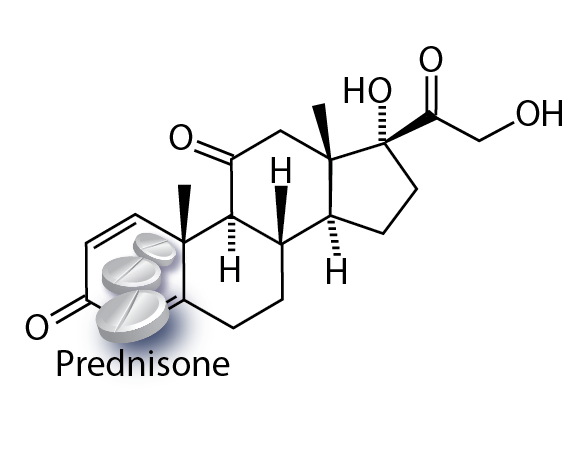

BioArt

Illustrating molecular method of action & drug delivery systems